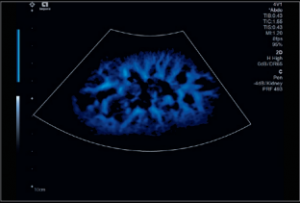

The Departments of Medical Physics and Radiology at the University of Wisconsin School of Medicine and Public Health provide a rich environment for performing research in Ultrasound Imaging (US). The infrastructure includes a wealth of equipment, support staff, and researchers with clinical and technical expertise. Please see below for a brief overview of the US equipment, personnel, and areas of ongoing research. You can also follow the links to see more information about the research program, or to apply for time on the US systems to conduct your own research project.

Housed within WIMR is a core group of investigators specializing in US research. This is a multi-disciplinary group, composed of faculty, post-docs, and students from the Departments of Medical Physics, Biomedical Engineering, Mechanical Engineering, Radiology, and others. The main emphasis of the research is developing new acquisition and analysis methods for enhancing the capabilities of clinical US imaging. Current projects focus on shear wave elastography, investigations of the underlying collagen microstructure of tissues, breast elastography, multi-scale/multi-modality imaging, platelet rich plasma injections and many other topics.

US research is performed by a number of investigators beyond the core group as well. Within the University of Wisconsin and throughout UW Health, there is a long-standing tradition of inter-departmental and inter-disciplinary collaborations that are necessary for advancing clinical and basic science. We work within multiple different project areas including Neurosurgery, OB, Orthopedics, Sports Medicine, Nephrology, the Laboratory for Optical and Computational Instrumentation, and many others.